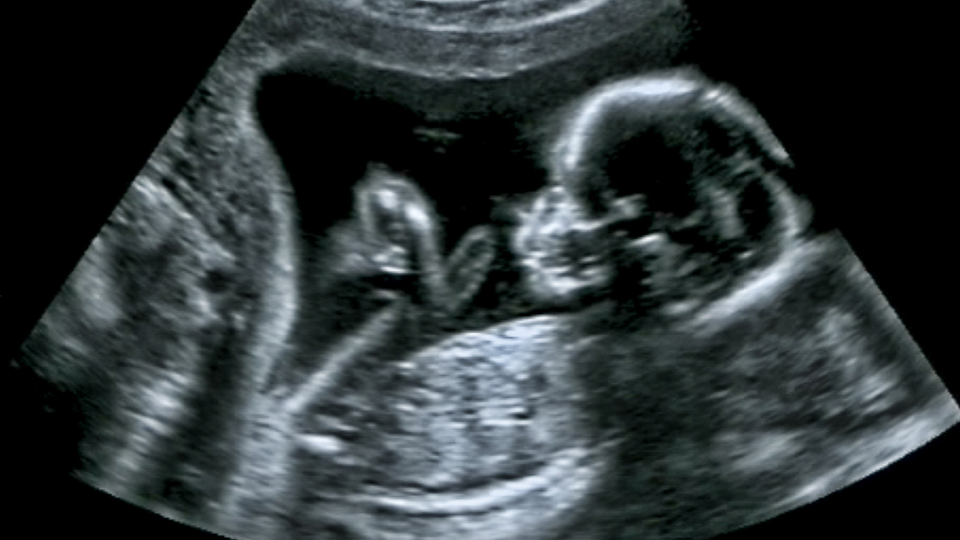

İnsan nesli tehlikede! "2045 yılında sperm sayısı "0" olacak"

Dünyaca ünlü Epidemiyolog Dr. Shanna Swan, bilimsel çalışmalarına dayandırdığı yeni kitabında; gelişmiş ülkelerdeki sperm sayısının giderek düştüğünü ve bu durumun `insanların hayatta kalmasını tehdit ettiğini' açıkladı. Swan, yaptığı tahminde sperm sayısının 2045'te sıfıra ulaşacağını belirtti

ABD´deki New York kentinde Mount Sinai Icahn Tıp Fakültesi'nde çevre ve üreme epidemiyolojisi uzmanı olan Dr. Shanna Swan, düşük sperm sayıların ve cinsel gelişimdeki değişikliklerin insan neslini tehlikeye atabileceğini açıkladı. Dr. Swan, "Count Down (Geriye Sayım)" adlı kitabında insanlığın doğurganlık kriziyle karşı karşıya kalacağını ifade etti. Swan, yaklaşan doğurganlık krizinin iklim kriziyle karşılaştırılabilir küresel bir tehdit oluşturduğu konusunda uyardı.

2017'de ortak yazarı olduğu bir araştırmanın ardından araştırmaya dayanarak hazırladığı kitabında, batıdaki sperm sayısının 1973 ile 2011 yılları arasında yüzde 59 oranında düştüğünü belirten Dr. Swan "Üreme olaylarının mevcut durumu, insan sağ kalımını tehdit etmeden daha uzun süre devam edemez" ifadelerini kullandı. Swan, mevcut tahminleri takiben medyan sperm sayısının 2045'te sıfıra ulaşacağını belirtti.